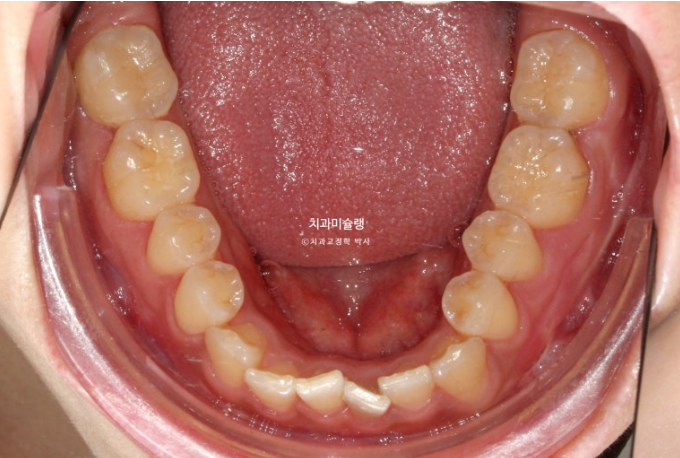

선수술 후 한달간의 회복기를 거쳐 25년 1월 본원에 내원했을 때의 교합 상태입니다.

25.01

아래 앞니 하나에 변색이 보입니다.

수술 직후 일시적으로 신경이 죽는 경우가 있으며 다시 돌아오기도 하니 일단 지켜봅니다.

앞니 두 개는 나비치아 돌출이며

어금니 교합이 떠있습니다.

앞니에 배열이 삐뚤합니다.

이 정도의 상태라면 14개 장치 안에서 해결이 가능합니다.

즉 인비절라인 라이트로도 충분합니다.